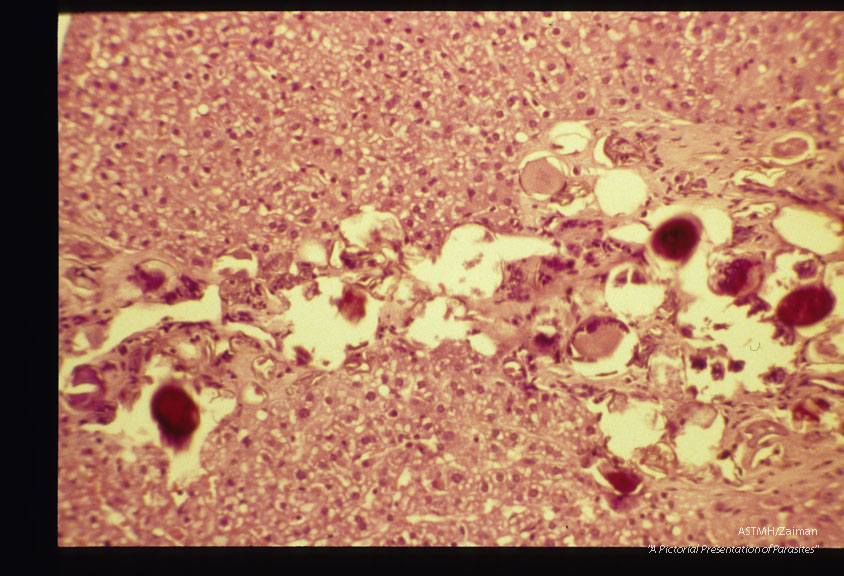

Eggs in armadillo (Dasypus novemcinctus) liver.

Heterobilharzia americana?

Description: Eggs in armadillo (Dasypus novemcinctus) liver.